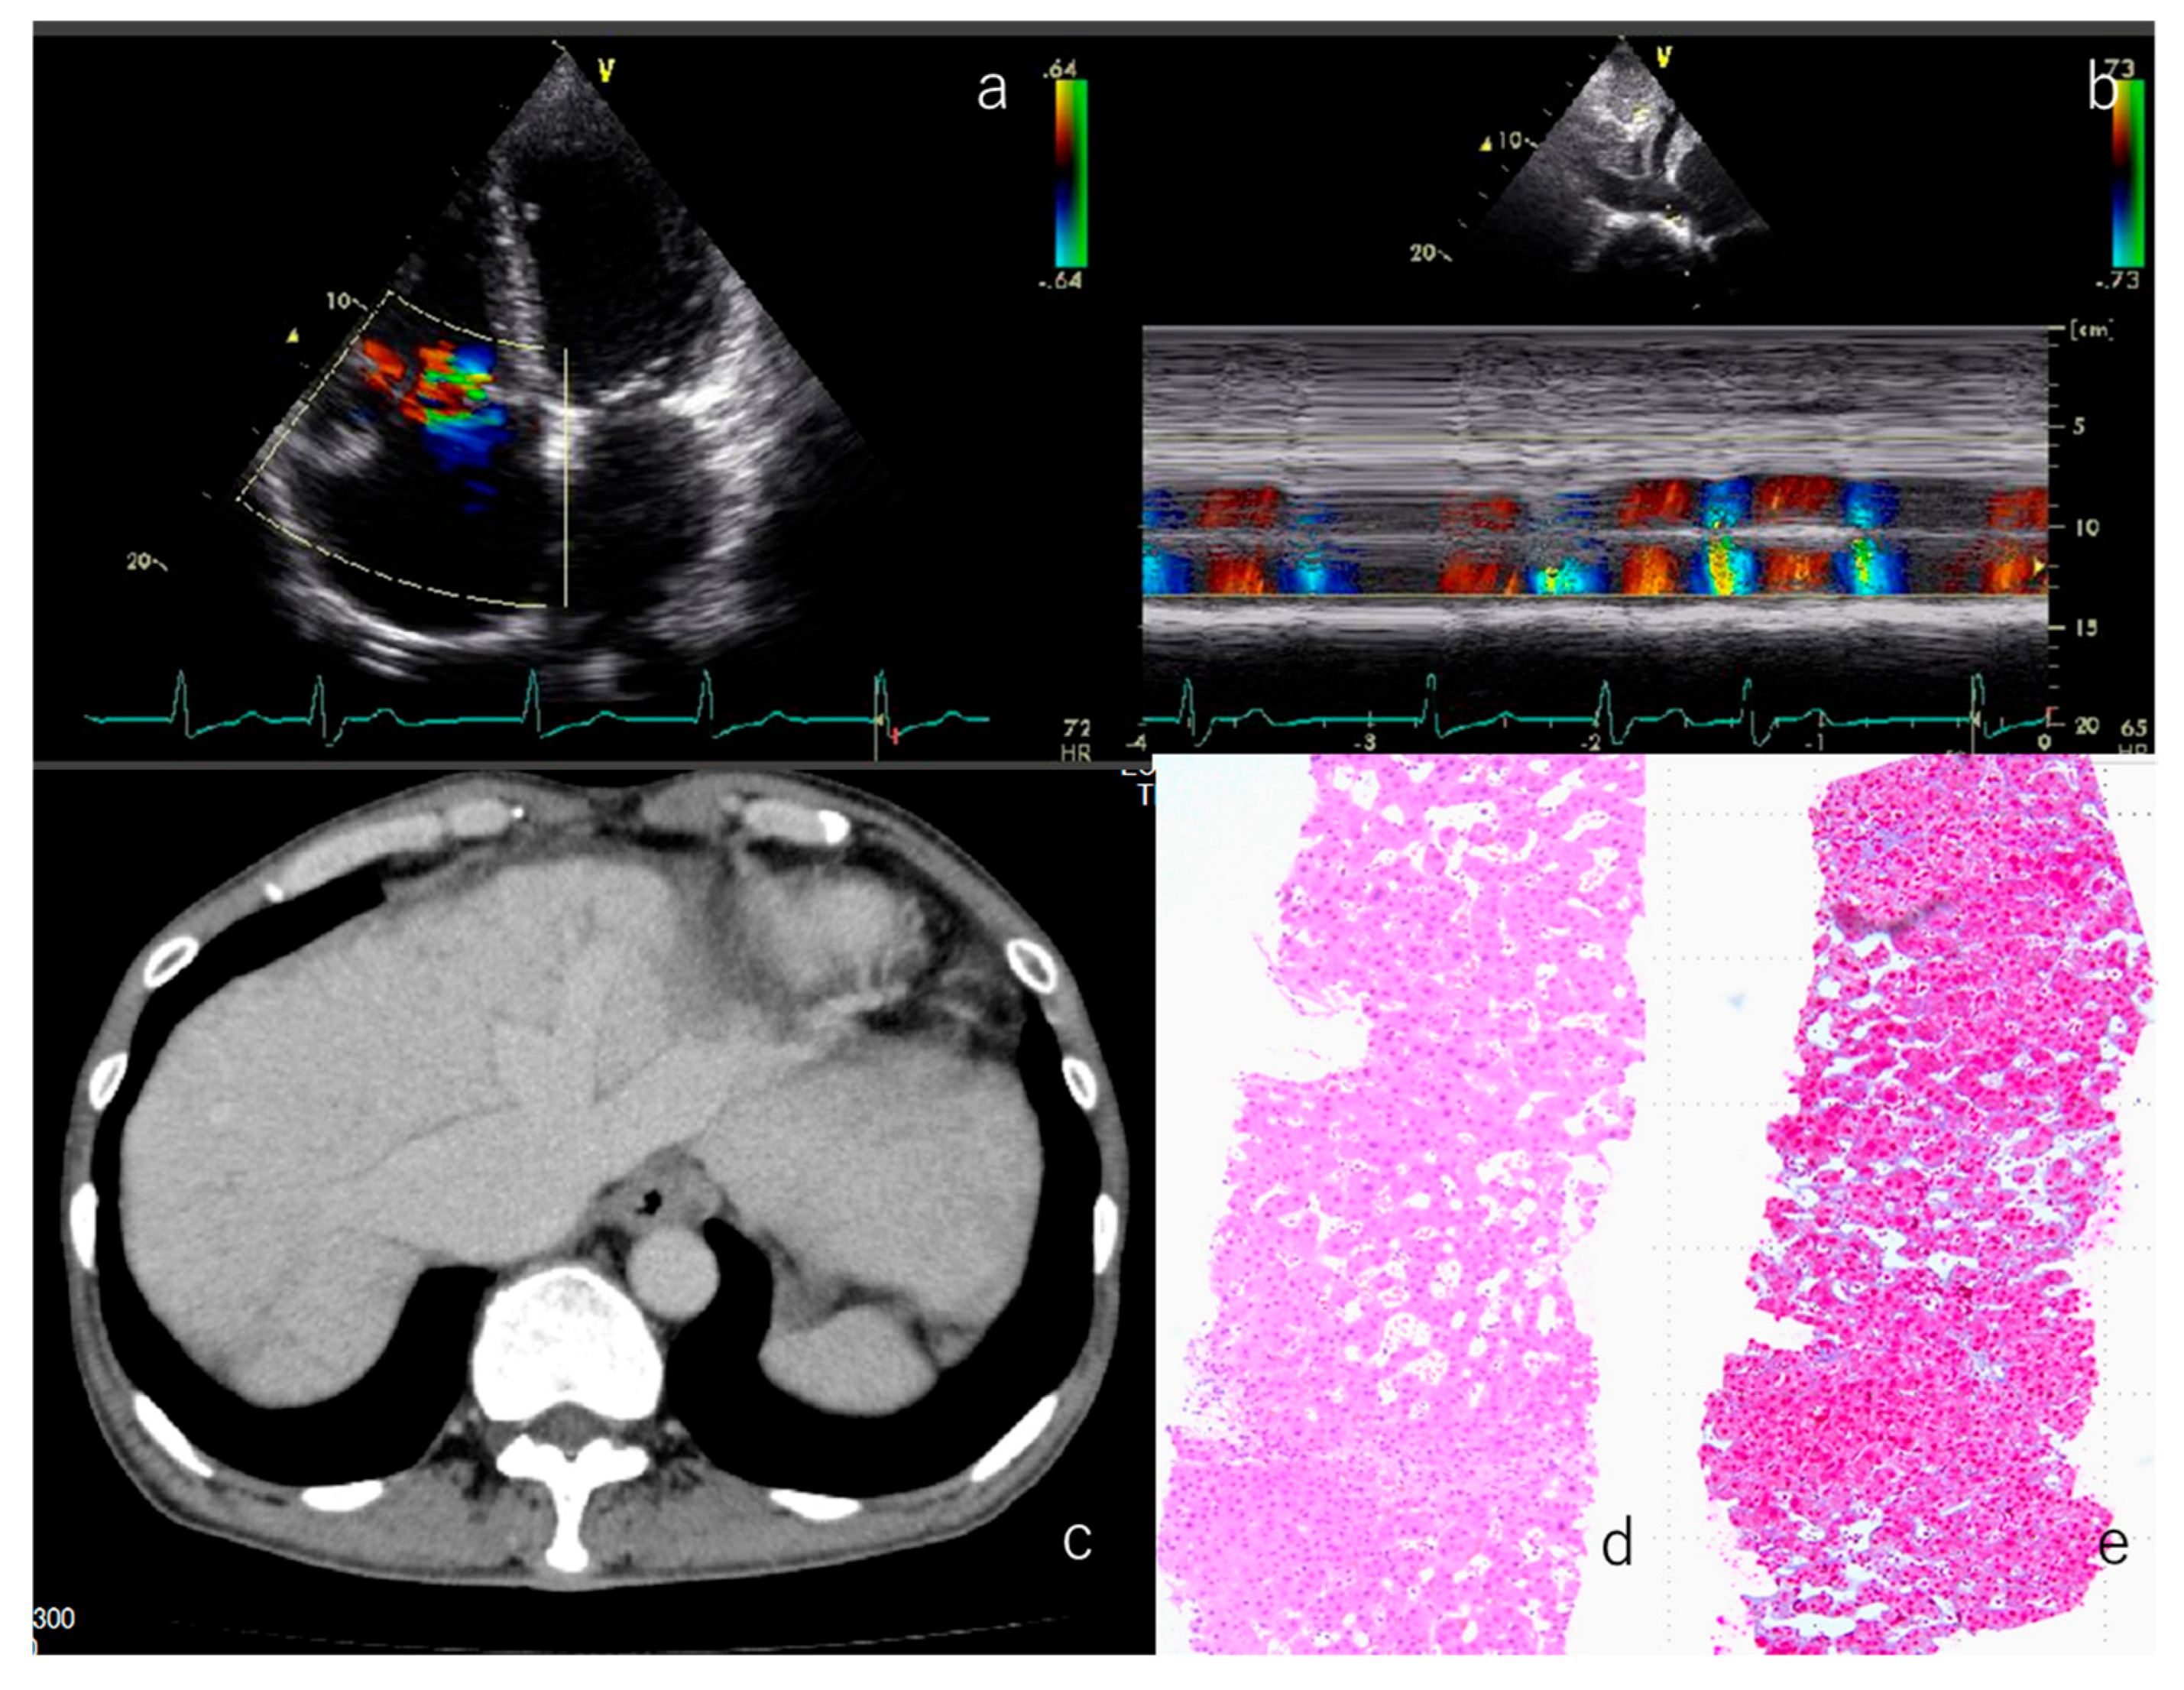

3.7. Representative Patient Exhibiting Typical Clinical Features Observed in the Study Cohort